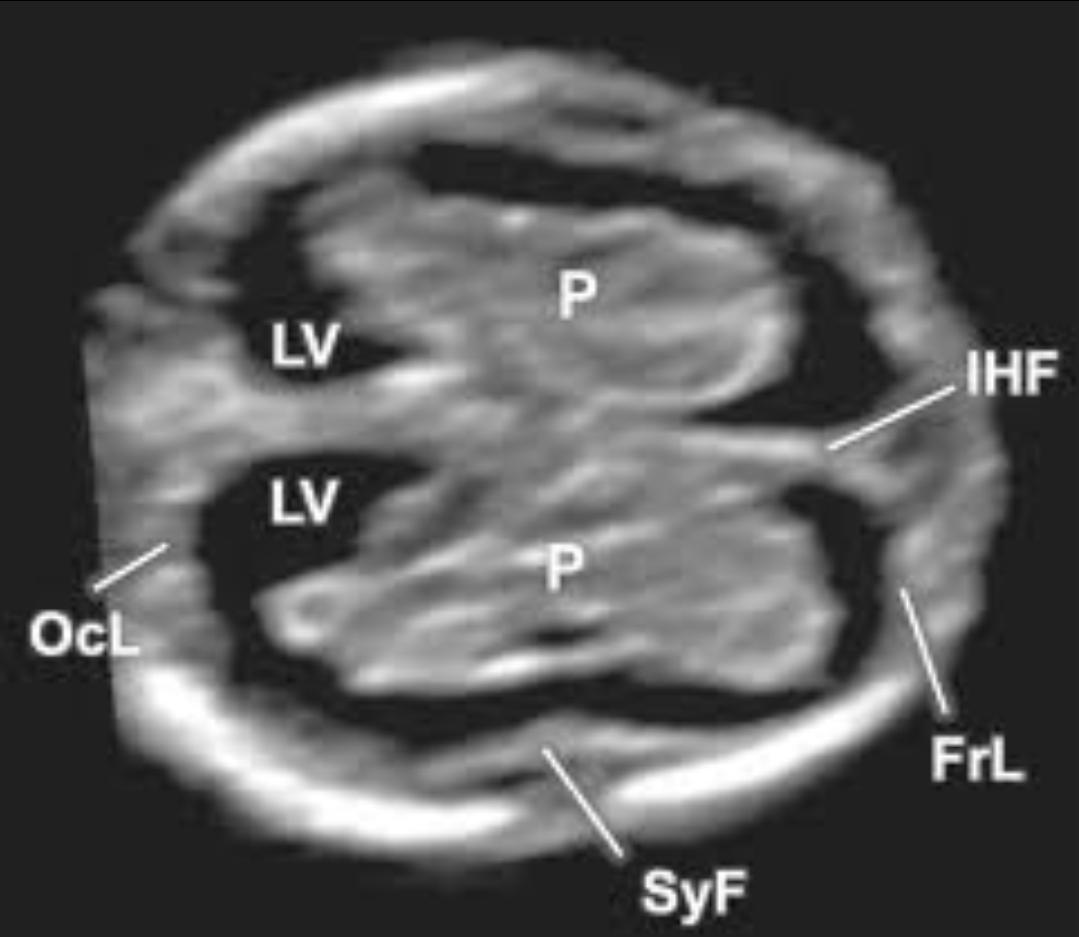

임신 10주 전후에서는 아직 대뇌 구조가 완전히 분화되지 않은 시기입니다. 초음파에서 흔히 말하는 “나비 모양”은 양측 측뇌실(choroid plexus 포함)이 대칭적으로 보이는 소견을 의미하는데, 이는 보통 임신 11주 후반에서 13주 무렵에 보다 명확하게 관찰됩니다. 10주에서는 해부학적 구조가 작고 두개골 석회화도 진행 중이라 단면 각도에 따라 나비 모양이 뚜렷하지 않게 보일 수 있습니다.

( 임신 10주 전후에서는 아직 대뇌 구조가 완전히 분화되지 않은 시기입니다. 초음파에서 흔히 말하는 “나비 모양”은 양측 측뇌실(choroid plexus 포함)이 대칭적으로 보이는 소견을 의미하는데, 이는 보통 임신 11주 후반에서 13주 무렵에 보다 명확하게 관찰됩니다. )

중요한 점은 이 시기에 뇌 구조 이상을 확정적으로 진단하기는 어렵다는 것입니다. 무뇌증(anencephaly)이나 심한 전뇌분할장애(holoprosencephaly)와 같은 중증 기형은 대개 이 시기에도 비교적 명확한 이상 소견을 보이지만, 단순히 “나비 모양이 뚜렷하지 않다”는 이유만으로 이상을 단정하지는 않습니다. 실제 임상에서는 주수 미달, 태아 자세, 프로브 각도, 복벽 두께 등의 영향으로 재확인을 권하는 경우가 흔합니다.